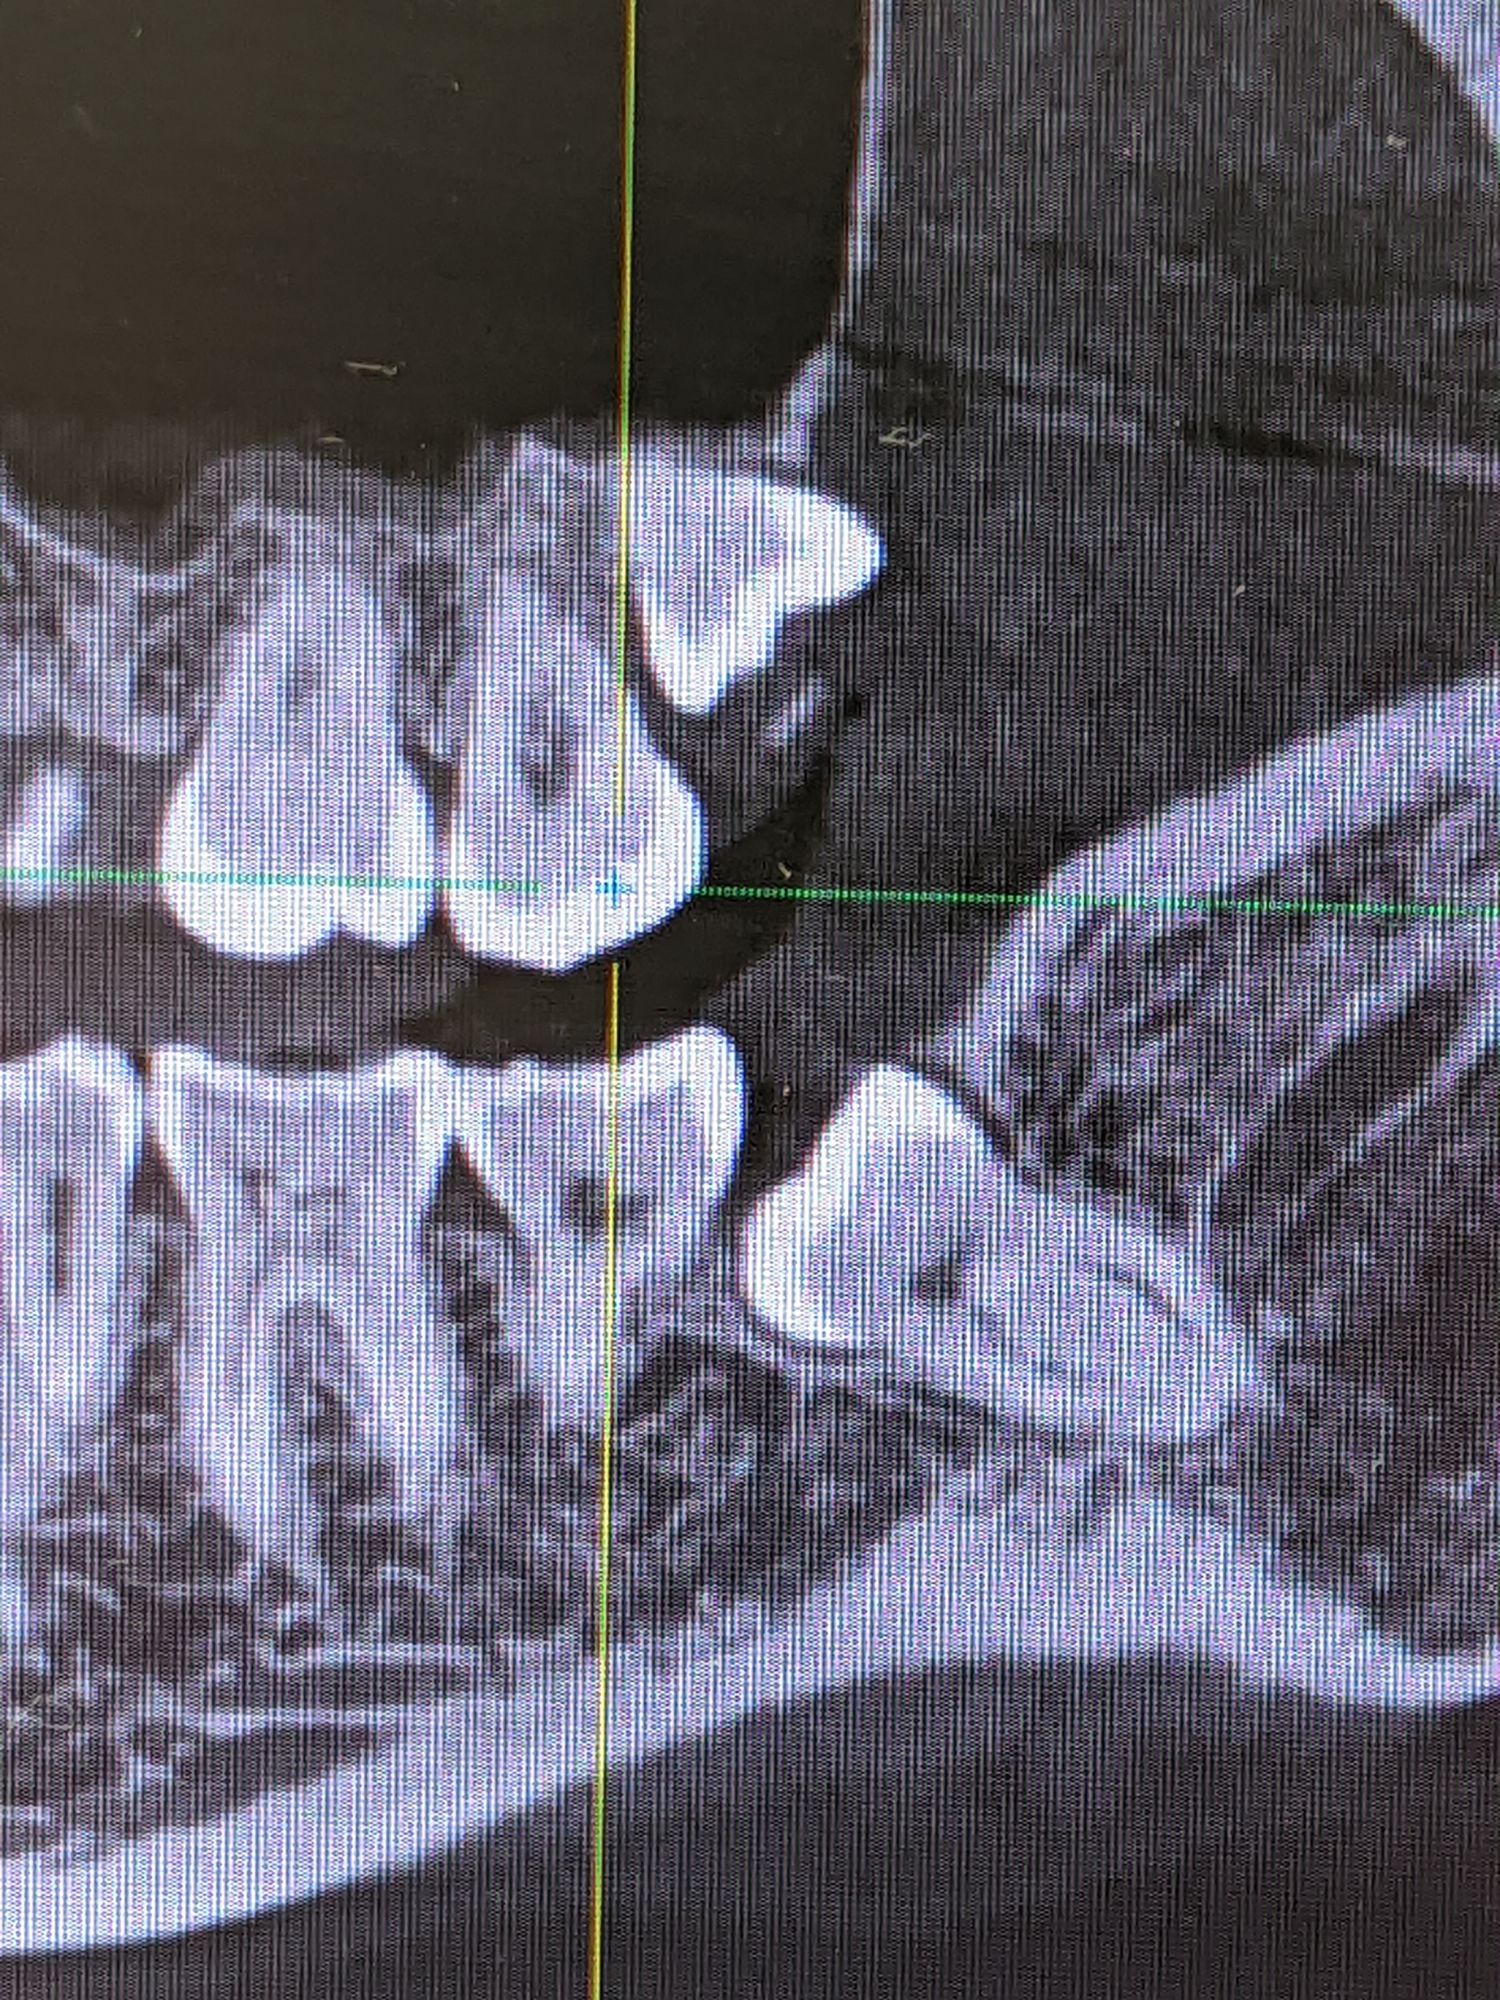

Удаление восьмых зубов вблизи нерва от 14 000 р.